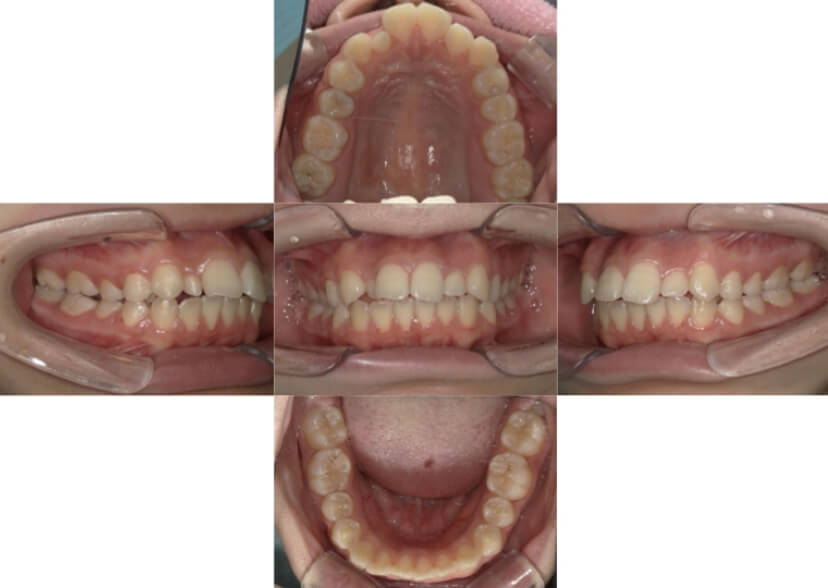

BEFORE

AFTER

上下顎叢生(上下の前歯のガタガタ)のケースです。

装置はラビアル(上下表側)で、上下顎の小臼歯を4本抜歯を行っています。抜歯したスペースを使って、上下の前歯の後方移動と叢生(ガタガタ)の改善を行っています。

主訴 八重歯を治したい。

年齢・性別 25歳 女性

お住まいの地域 神奈川県川崎市

治療方針 抜歯スペースを利用して上前歯の叢生(ガタガタ)の改善

抜歯部位 上下顎左右第一小臼歯

使用装置 ラビアル(上下表側)、顎間ゴム

治療期間 1年11か月

治療回数 16回

リテーナー クリアリテーナー